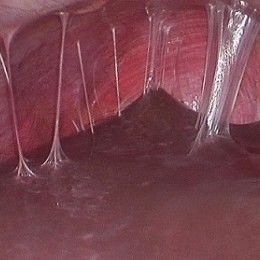

Hội chứng Asherman là một tình trạng hiếm gặp, mắc phải của tử cung. Hội chứng này xảy ra sau khi nạo thai hoặc nạo tử cung sau sinh, nhất là khi tử cung có sự nhiễm trùng. Ngoài ra, còn do thủ thuật phẫu thuật lấy thai...gây tổn thương nội mạc dẫn tới ít kinh, vô kinh, thậm chí là vô sinh. Bệnh đặc trưng bởi sự hình thành của các vùng dính (mô sẹo) trong tử cung hoặc cổ tử cung dẫn đến khoang tử cung hẹp [14-16].

Hình ảnh hội chứng Asherman